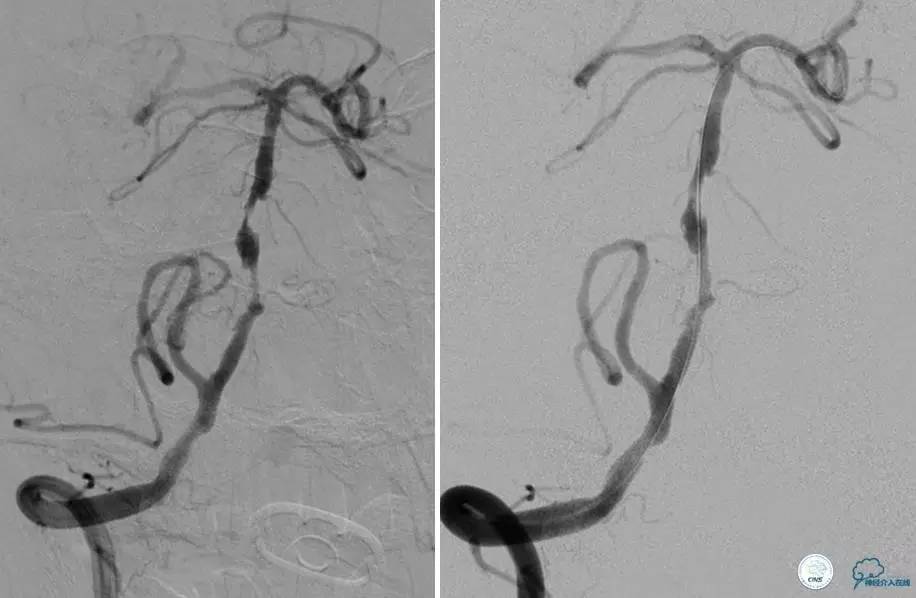

▼DSA示右侧椎动脉发育低下,弥漫性狭窄,可以看到左侧椎动脉反流,因此判断左侧椎动脉V4段CTO。

微导丝穿过闭塞段,微导管造影,球扩闭塞段,置入Wingspan支架,血流完全恢复正常。

患者术后2天再次出现卒中发作,药物治疗好转,此后病情稳定。半年后复查DSA,见支架闭塞,侧支循环开放。患者一般情况好,mRS:1分。